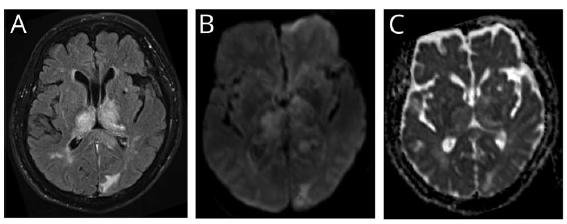

▍脑脊液检查:脑脊液压力15 cm H2O,脑脊液蛋白115.1mg/dL (参考范围:15 - 45 mg/dL),细胞数、葡萄糖和氯化物正常范围。脑电图示弥漫性慢波。颅脑MRI示双侧丘脑T2高信号并延伸至左侧胼胝体压部,伴轻度弥散受限,增强扫描可见散在强化。梯度回波成像示左侧外囊、右侧枕叶内侧点状微出血病灶。

颅脑MRI示左侧颞叶内侧、左侧枕叶和双侧丘脑T2高信号伴明显水肿,需要考虑血管性疾病。

双侧丘脑受累的卒中需要考虑Percheron动脉梗死。这种变异的血管起源于大脑后动脉近端,分叉后供应双侧丘脑。Percheron动脉闭塞可导致双侧丘脑梗死,部分患者可伴中脑受累。

另外,静脉梗死也需要考虑。MRI病灶相对对称、脑深部T2高信号伴水肿且不符合动脉分布。CTV示直窦部分缺失或发育不全,而无明确充盈缺损支持血栓形成。然而,可见静脉侧枝建立征象,提示静脉窦系统慢性静脉闭塞过程。由于CTV显示的是一种慢性甚至是发育过程,因此仍无法明确这种静脉异常与急性认知功能下降和神经影像改变是否相关。

其他可能需要鉴别的疾病包括CJD、韦尼克脑病、病毒性脑炎和自身免疫性脑炎。尽管CJD患者MRI可出现双侧丘脑异常信号,但无明显水肿或占位效应。

此外,CJD在DWI上还可出现“皮层绸缎征”。韦尼克脑病也可出现双侧丘脑受累,但其他典型部位如乳头体、导水管周围、顶盖和三脑室周围结构未受累。